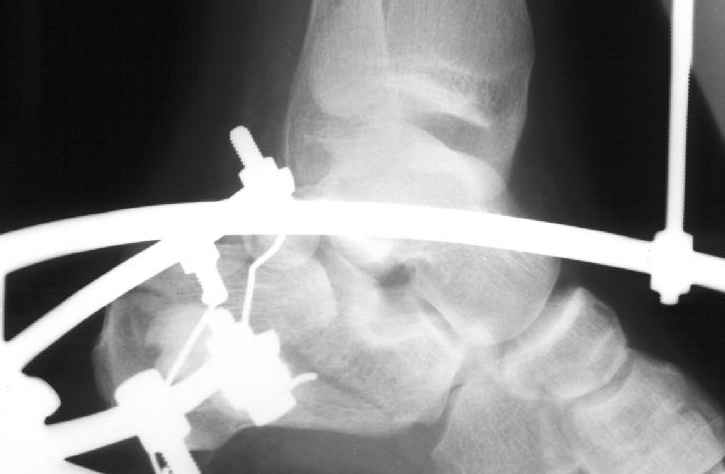

В/суставные переломы пяточной кости у молодых являются показанием к оперативной коррекции, Большой материал накоплен у д-ра Дрягина (Челябинск). В нашем отделении предпочтение отдаем открытой репозиции, при наличии выраженного отека, фликтен и т.д.

Накладываем спицевой дистрактор, позволяющий выхаживать м/ткани и одновременно устранять захождение отломков.

Окончательная фиксация спицами, пяточными пластинами (5) , в последнее время стали применять крючковидные пластины (ДЕОСТ) (6,6a).